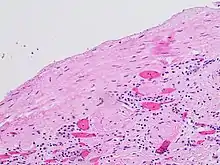

Diagnosis

The complex cyst can be further evaluated with doppler ultrasonography, and for Bosniak classification and follow-up of complex cysts, either contrast-enhanced ultrasound (CEUS) or contrast CT is used.[12]